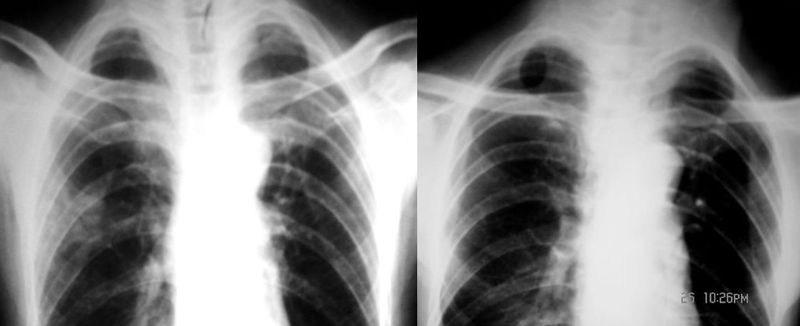

球形肺炎是大叶性肺炎的一种特殊表现[1],以肺的渗出实变为主。它的机理未明,可能是由于抗生素的广泛应用,大叶性或节段性肺炎发展受到限制而形成球形,其形成又与病缘菌的毒性数量及机体的免疫能力有关。病人多有感然症状,某些病人无明显感然症状。病变呈球形或椭圆形,大小不等,病灶密度多均匀,ct值稍低于软组织密度;或中央密度高,边缘密度低,显示晕圈状改变;有时可见空洞[2]。病灶边缘比较规则,也可不规则,有毛刺或呈锯齿状改变,但较模糊。位于肺周区,贴近胸膜,部分病栽表现为两侧缘垂直于胸膜,呈刀切样平直边缘。病灶周围血管纹理增多、增粗、常有局限性胸膜增厚。球形肺炎抗炎两周后,病灶即有缩小,最后能完全吸收。

球形肺炎:病变密度相对较淡,中央密度略高,ct图片上密度较为均匀,增强中央可出现无强化区。病变邻近胸膜反应较为显著,可表现为增厚、粘连(可以比较广泛),病变内可以见到大血管的贯穿,周围及近肺门侧可以见到血管纹理增多、增粗,可有支气管充气征象,两侧可垂直于胸膜或呈方形,边缘可为刀切征,它可以出现毛刺样的类似改变,短期内抗炎治疗有效。

③球型肺炎:中央密度高边缘较淡,呈晕样改变;广泛胸膜增厚;病灶呈方形,周围可见斑状、薄片影,周围血管纹理多、增粗,无僵直和牵拉;临床上有起病急变化快,抗炎治疗效果明显,病程短等特征。